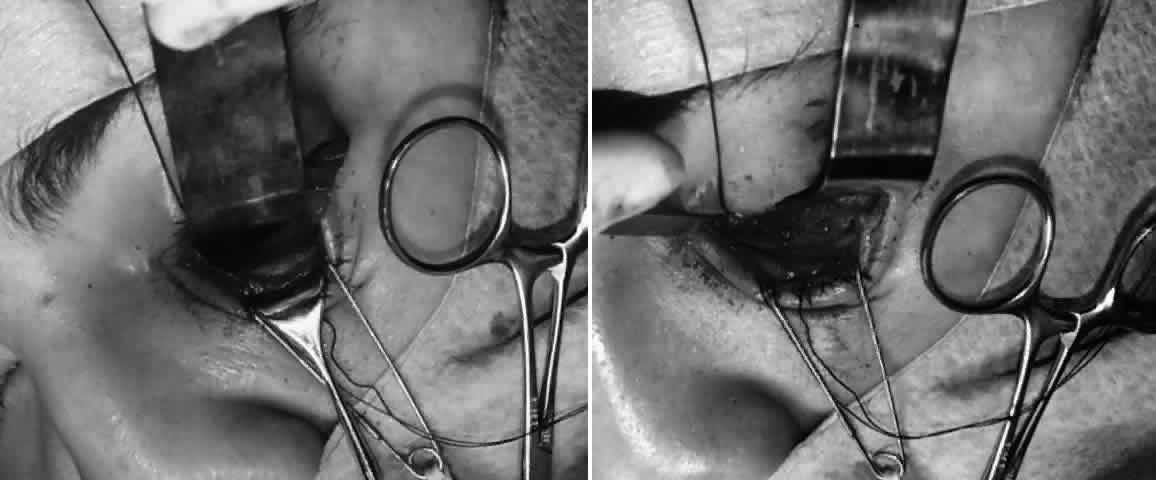

with stainless steel, with titanium having the least artifact.  Fig. 8. A. Patient with right zygomatico-orbital fracture. Note flattening of right

malar eminence and slight right lateral canthal dystopia. B. Axial CT scan shows displaced right zygomatico-orbital fracture. Fig. 8. A. Patient with right zygomatico-orbital fracture. Note flattening of right

malar eminence and slight right lateral canthal dystopia. B. Axial CT scan shows displaced right zygomatico-orbital fracture.

Fig. 9. Repair of zygomatico-orbital fracture with rigid miniplate fixation, approached

via a single transconjunctival incision with extended lateral

canthotomy/cantholysis. A. Exposure and fixation of lateral (frontozygomatic) orbital rim fracture. B. Reduction and fixation of inferior orbital rim fracture. Orbital floor

can also be explored via the same approach. Fig. 9. Repair of zygomatico-orbital fracture with rigid miniplate fixation, approached

via a single transconjunctival incision with extended lateral

canthotomy/cantholysis. A. Exposure and fixation of lateral (frontozygomatic) orbital rim fracture. B. Reduction and fixation of inferior orbital rim fracture. Orbital floor

can also be explored via the same approach.

Fig. 10. A. Postoperative appearance of patient in Figure 8 showing excellent position of the globe and eyelid. B. Normal malar contour has been re-established. Fig. 10. A. Postoperative appearance of patient in Figure 8 showing excellent position of the globe and eyelid. B. Normal malar contour has been re-established.